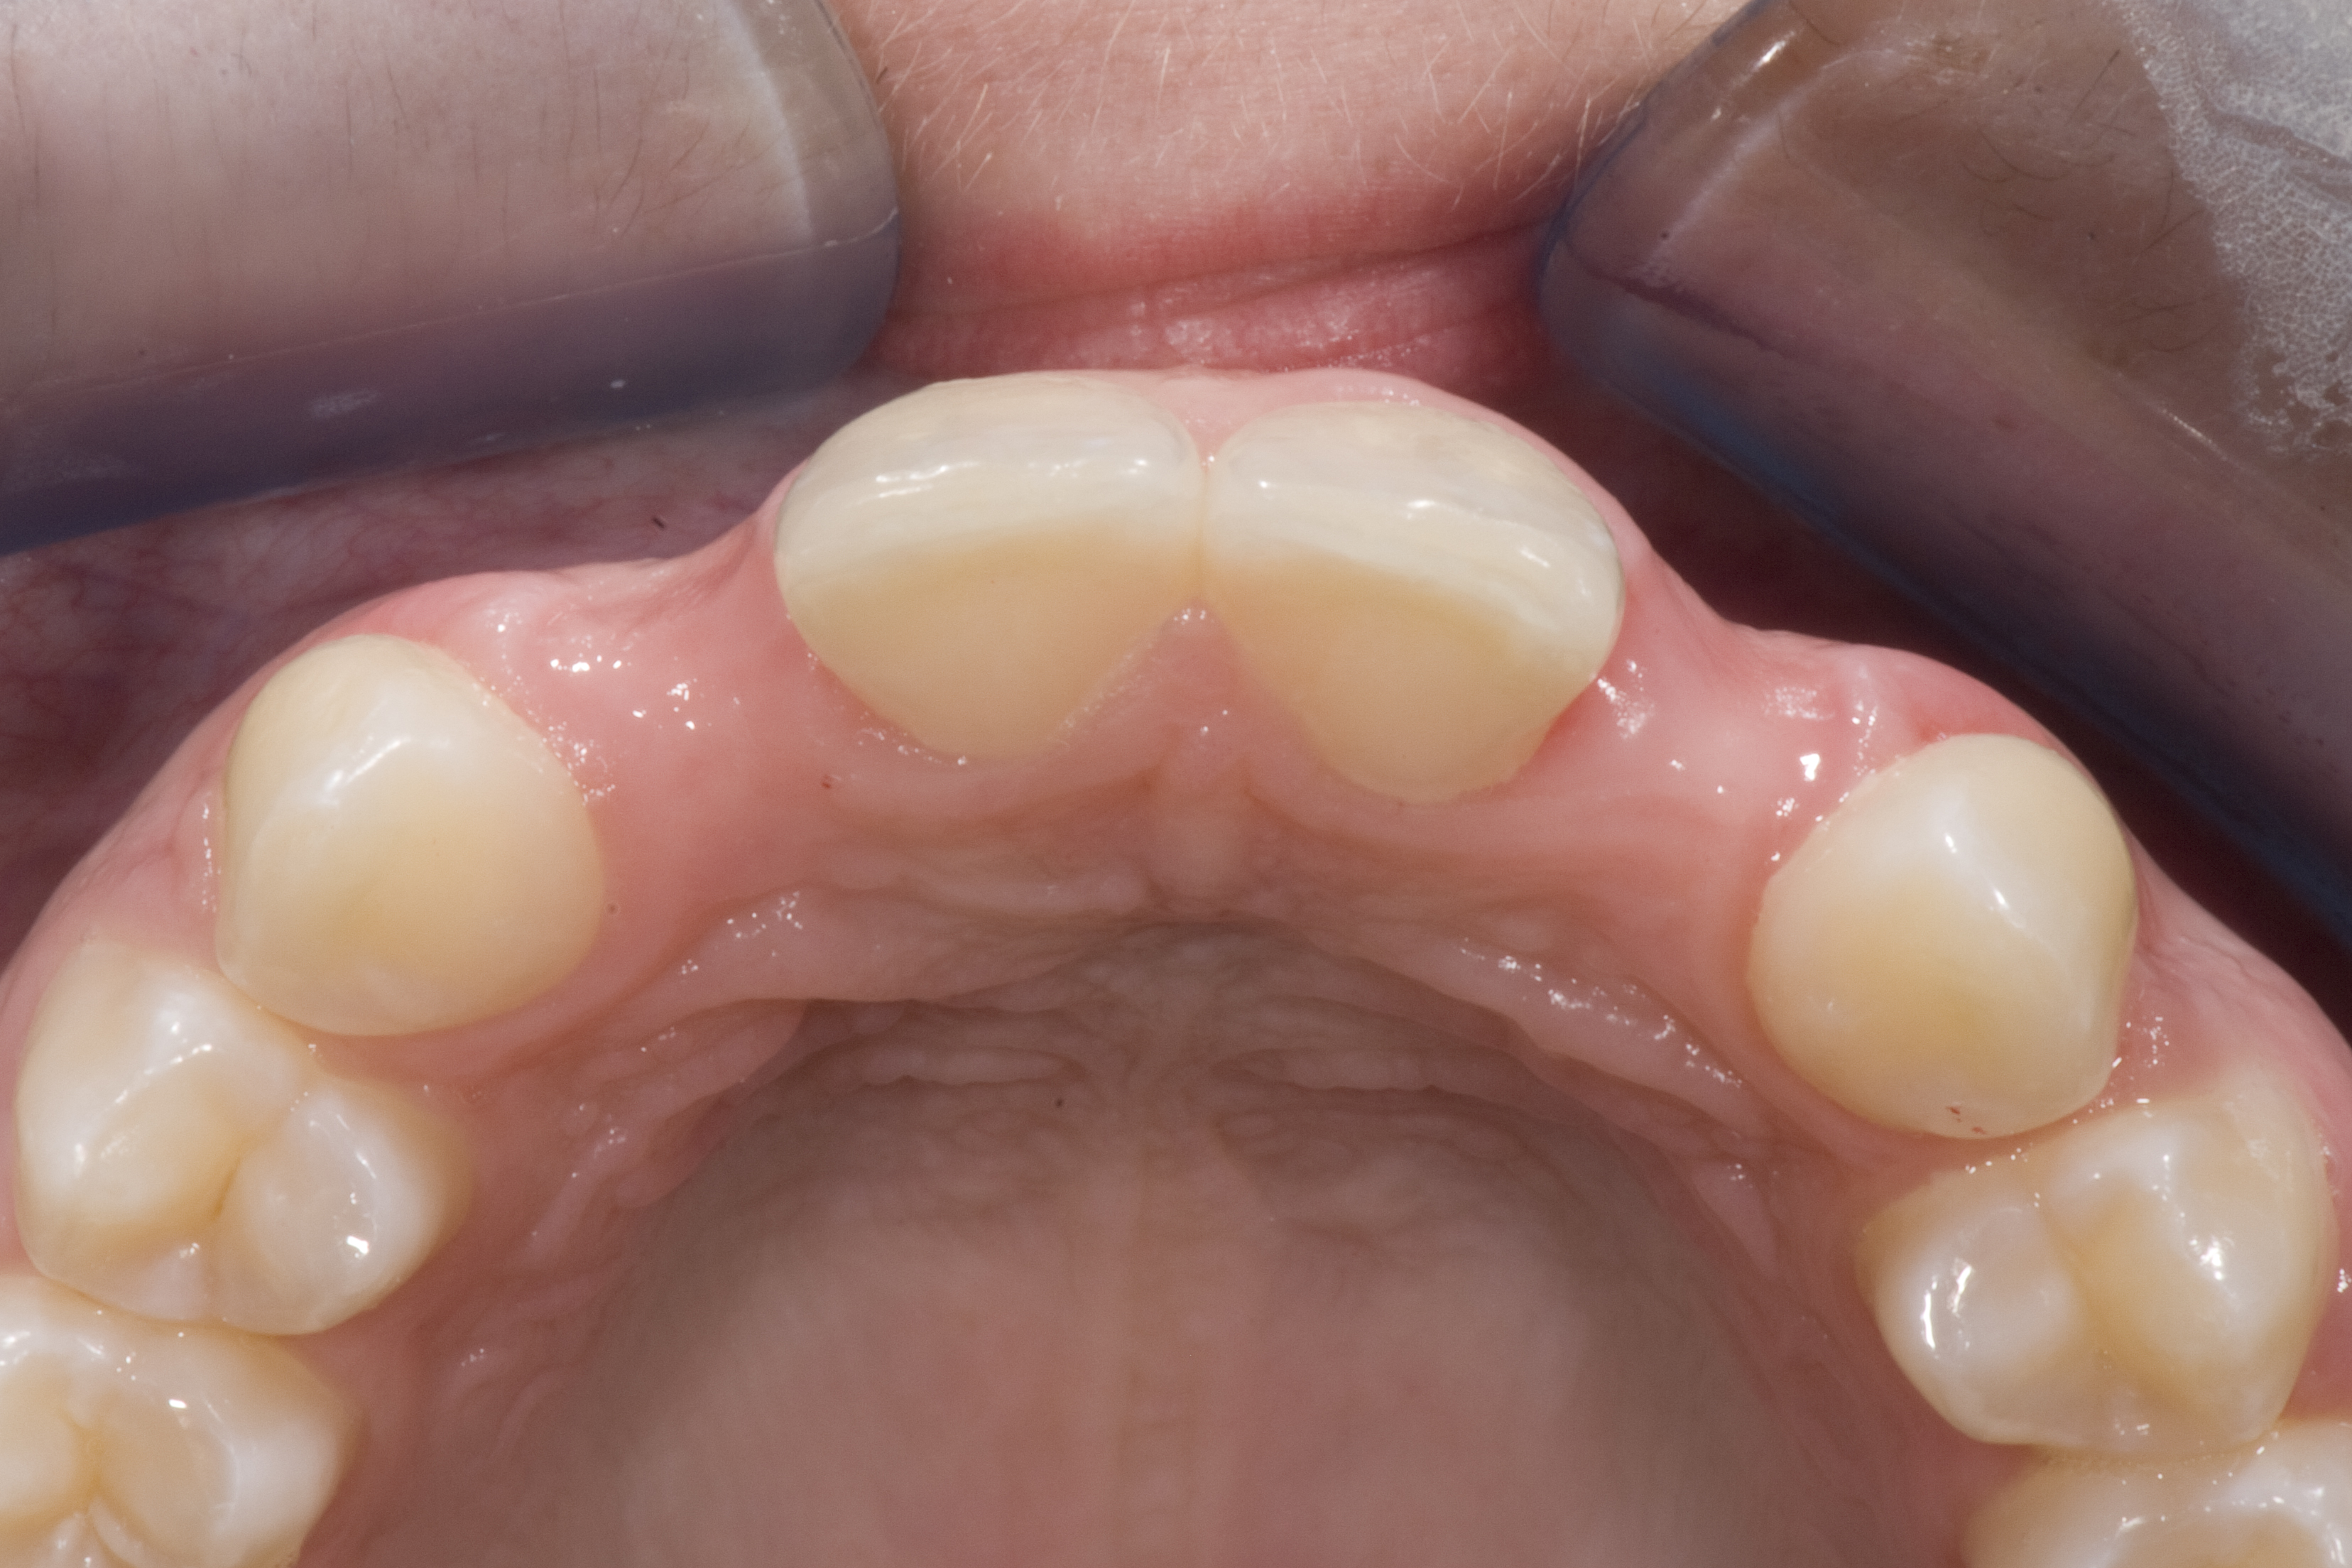

A 14-year-old patient presented to the office with his mother (Figure 1). His chief complaint involved the large spaces between the teeth created by his missing right maxillary lateral incisor and his small left maxillary lateral incisor. He desired to replace the missing tooth with an implant and create a beautiful smile. Upon examination, he was found to have a class I canine and molar relationship, but because he had a tooth size/arch size discrepancy and space distal to the right central incisor, the remaining incisors had drifted to the right. The left maxillary lateral incisor was peg-shaped and in a cross bite position. Studies have shown a clear association between congenitally missing teeth and reduced tooth size.59-62 Because he was only 14-years-old at the time and could not have implants placed until the cessation of growth (somewhere in the vicinity of 22 years old), he was sent to the orthodontist for alignment of the teeth.16,17 After 2 years of orthodontics, the appliances were removed, and his tooth coloration was improved using carbamide peroxide bleaching (Figure 2). Because some form of provisional needed to be placed until he was finished growing, a double-wing metal resin-bonded bridge was chosen. As discussed earlier, this is the ideal transitional prosthesis for patients that have congenitally missing maxillary lateral incisors. The benefits of this type of prosthesis include its ability to be removed and rebonded during the surgical phase of treatment and its ability to retain the roots in their proper position after orthodontic treatment.16 The final plan for the patient was to increase the width of the central and the maxillary left lateral incisor, utilizing porcelain laminate veneers to achieve the appropriate width/length ratio of 80%. A wax-up was created to idealize tooth size, a putty matrix was made from the wax-up to facilitate bonding of the incisors, and a non-precious, double-wing metal resin-bonded bridge was fabricated for lateral incisor replacement. Once the teeth were bonded to ideal size, the “Maryland Bridge” was fabricated from a polyvinyl arch impression with the newly bonded teeth (Figure 3). The metal frame was cast from a non-precious alloy to allow for fabrication of a very thin frame and to create a better surface for bonding. After sandblasting the internal aspect of the frame with CoJet™ silica (3M ESPE), accomplishing salinization, and executing cementation with a dual-cure resin cement, a fairly good adhesion to the frame was anticipated.29 The enamel surface was etched with phosphoric acid for 30 seconds, the primer (Single Bond Plus, 3M ESPE) was applied to both the internal surface of the sandblasted framework and the etched enamel, and the bridge was cemented with RelyX™ ARC (3M Espe) dual-cured resin cement (Figure 4 and Figure 5).

(3.) After resin-based composite bonding of the three incisors.

Figure 3